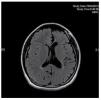

A 13-year-old female, product of a fourth pregnancy, with a history of a monozygotic twin pregnancy, full term with adequate weight and no contingencies, normal psychomotor development up to the first year of age, when a gait alteration with right hemibody weakness was noticed. She was admitted to the Pediatric Neurology Service at "Dr. José Eleuterio González" University Hospital after presenting simple partial seizure with motor symptoms at age 7. An electroencephalogram (EEG) was performed with normal results, and the patient was controlled with 400 mg/day of oral carbamazepine. During the physical exam the patient displayed hemifacial atrophy of the right side causing asymmetry (Fig. 1), right spastic hemiparesis with atrophy, hyperreflexia, ipsilateral extensor plantar response and a hemiplegic gait. We are able to observe in the brain MRI a reduction of ridges and grooves in the left frontoparietal region, associated with ectasia of the ipsilateral ventricle, which is compatible with cerebral hemiatrophy of the left frontoparietal lobe (Figs. 2 and 3). The patient is currently stable with proper control of seizure crisis and an adequate level of antiepileptic medication (9.0 µg/dl). She is attending our integral follow-up service and rehabilitation.

Figure 2 Axial magnetic resonance imaging (MRI), T2 FLAIR sequence which shows left frontoparietal atrophy with ipsilateral ventriculomegaly.

Figure 3 Coronal magnetic resonance imaging (MRI), T2 FLAIR sequence which shows interhemispheric asymmetry with atrophy and left ventricular ectasia.